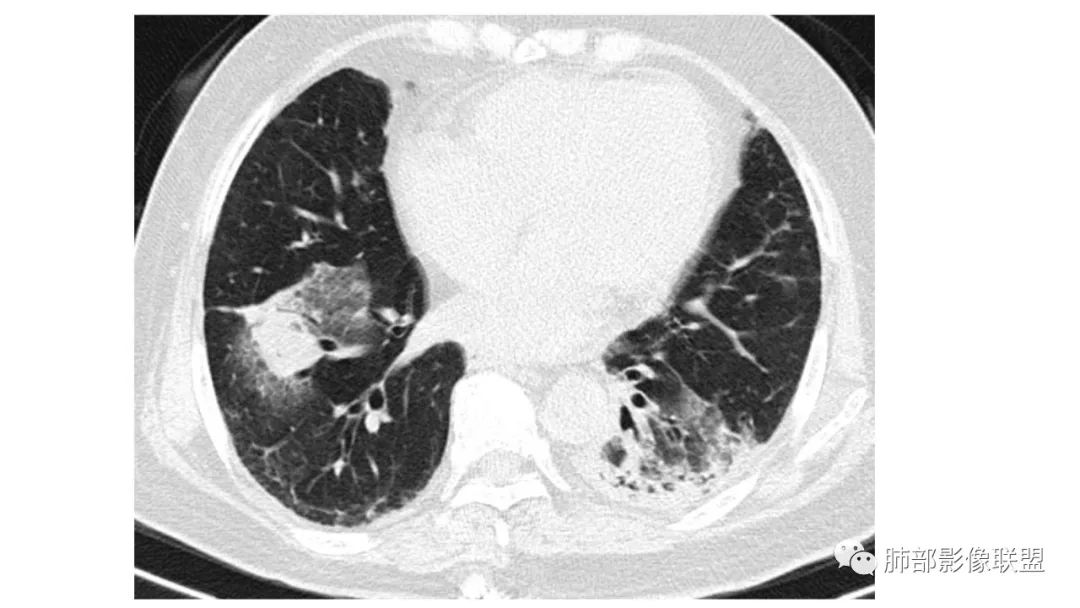

二、肺炎型

2、病灶常有一个主病灶,常位于下肺。后沿气道播散为多发病灶。

3、重力作用,叠瓦征。近叶间裂因重力效应,呈膨隆改变。

4、增强后不均匀强化,存在低强化区呈弱强化或无强化,因此可见“血管造影征。”血管毛糙与肺炎有统计学差异。

5、支气管粗细不均,呈“枯树枝征”,但与肺炎这一点鉴别不具有统计学差异。可发生支气管扩张

6、空腔形成,部分蜂窝状改变。

8、斑片常伴有结节,边缘清楚GGO或欠清楚。